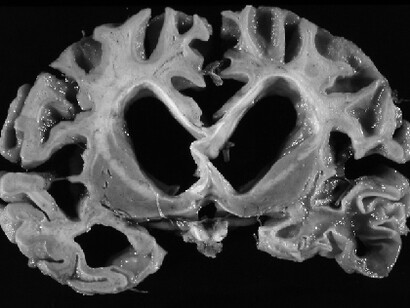

El mecanismo inicial de infección parece ser el reconocimiento y fusión por parte de la proteína S denominada espiga (spike) de la superficie del SARS-CoV-2 con el receptor para la enzima convertidora de angiotensina 2 (ACE2) en humanos; esta última expresada en el endotelio capilar del cerebro y multitud de órganos. En relación con esta información, recientemente se ha demostrado la presencia de SARS-CoV-2 en muestras de autopsias a nivel del SNC en los revestimientos endoteliales en las áreas adyacentes a las áreas necróticas en pacientes enfermos de COVID-19. Además, se ha aislado SARS-CoV-1 del tejido cerebral con edema neuronal y degeneración a partir de autopsias. Todo esto se ha llevado a cabo con métodos de inmunohistoquímica, hibridación in situ y confirmación microscópica electrónica de la infección viral de neuronas.